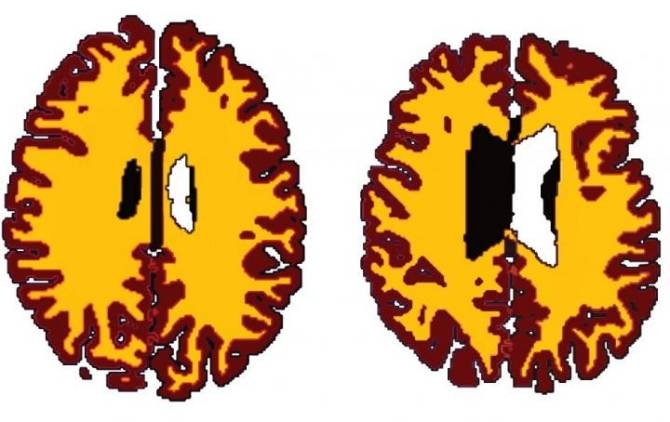

Los autores del estudio dividieron los datos en dos categorías con arreglo al peso: sujetos delgados y sujetos con sobrepeso. Hallaron diferencias sorprendentes en el volumen de la materia blanca en los cerebros de las personas con sobrepeso comparado con el de sus homólogos más delgados. Las personas con sobrepeso examinadas tenían una reducción generalizada en la materia blanca, en comparación con las delgadas.

El equipo calculó entonces cómo estaba relacionado el volumen de materia blanca con la edad en los dos grupos. Descubrieron que una persona con sobrepeso de, digamos, 50 años, tenía un volumen de materia blanca comparable con el de una persona delgada de unos 60 años, lo que implica una diferencia en la edad cerebral de aproximadamente 10 años.